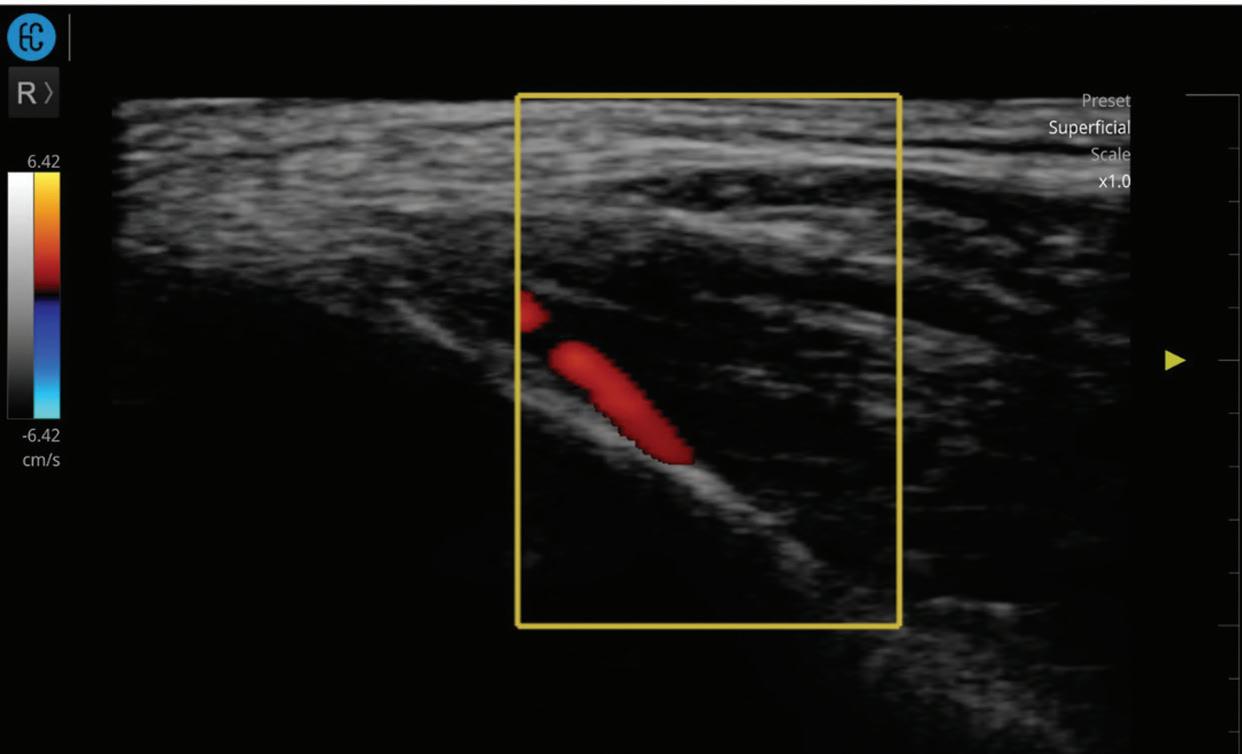

42 Anatomy-based filler placement in the temple using e.p.t.q.®: The role of ultrasound imaging

Edmond Lau, MD, explores how real-time ultrasound guidance and e.p.t.q.®’s tailored HA fillers combine to offer safer, more targeted aesthetic outcomes